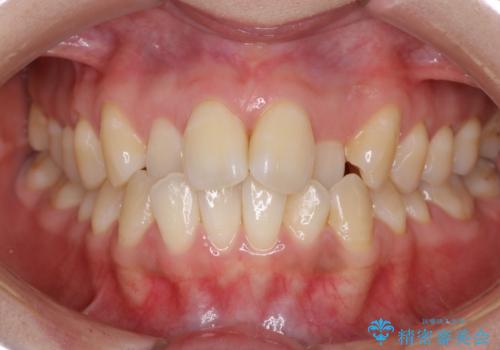

【インビザライン】正中離開を治したい

再矯正ということでがたつきはなくきれいに並んでいましたが、上下のアーチ(歯列弓)の大きさのバランスが悪く、結果的に後戻りの原因になってしまっていました。今回は下のアーチを小さくするためにIPRを行い、かみ合わせのバランスを治しながら前歯の隙間を閉じました。